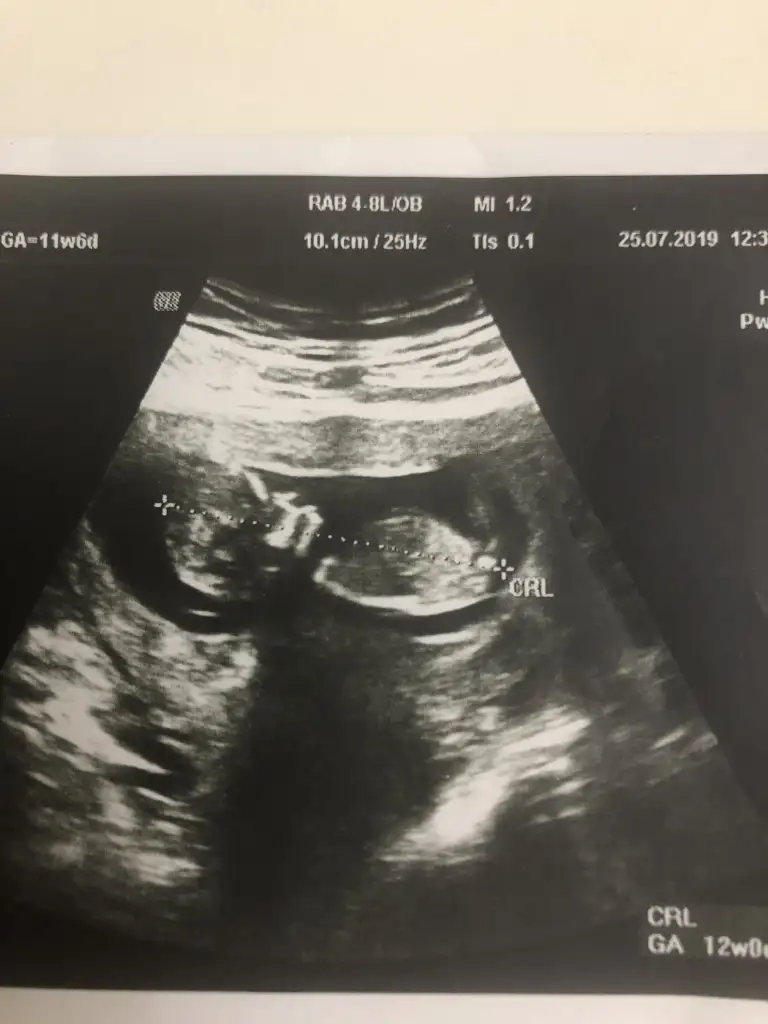

Erkek gibi kafa sekline yorumluyorum nub artık olmaz 13 hafta sanırımArkadaşlar daha önce yorum yapmıştınız ama doktor kesin bişey söylemiyor bunada bakabilir misiniz

Evet teşekkür ederimmmErkek gibi kafa sekline yorumluyorum nub artık olmaz 13 hafta sanırım

KizzArkadaşlar daire içine aldığım yermi nub oluyor bide yorumlayabilirmisiz lütfen

Tam dik degil ama ben tahminimi Erkek gibi yorumluyorum